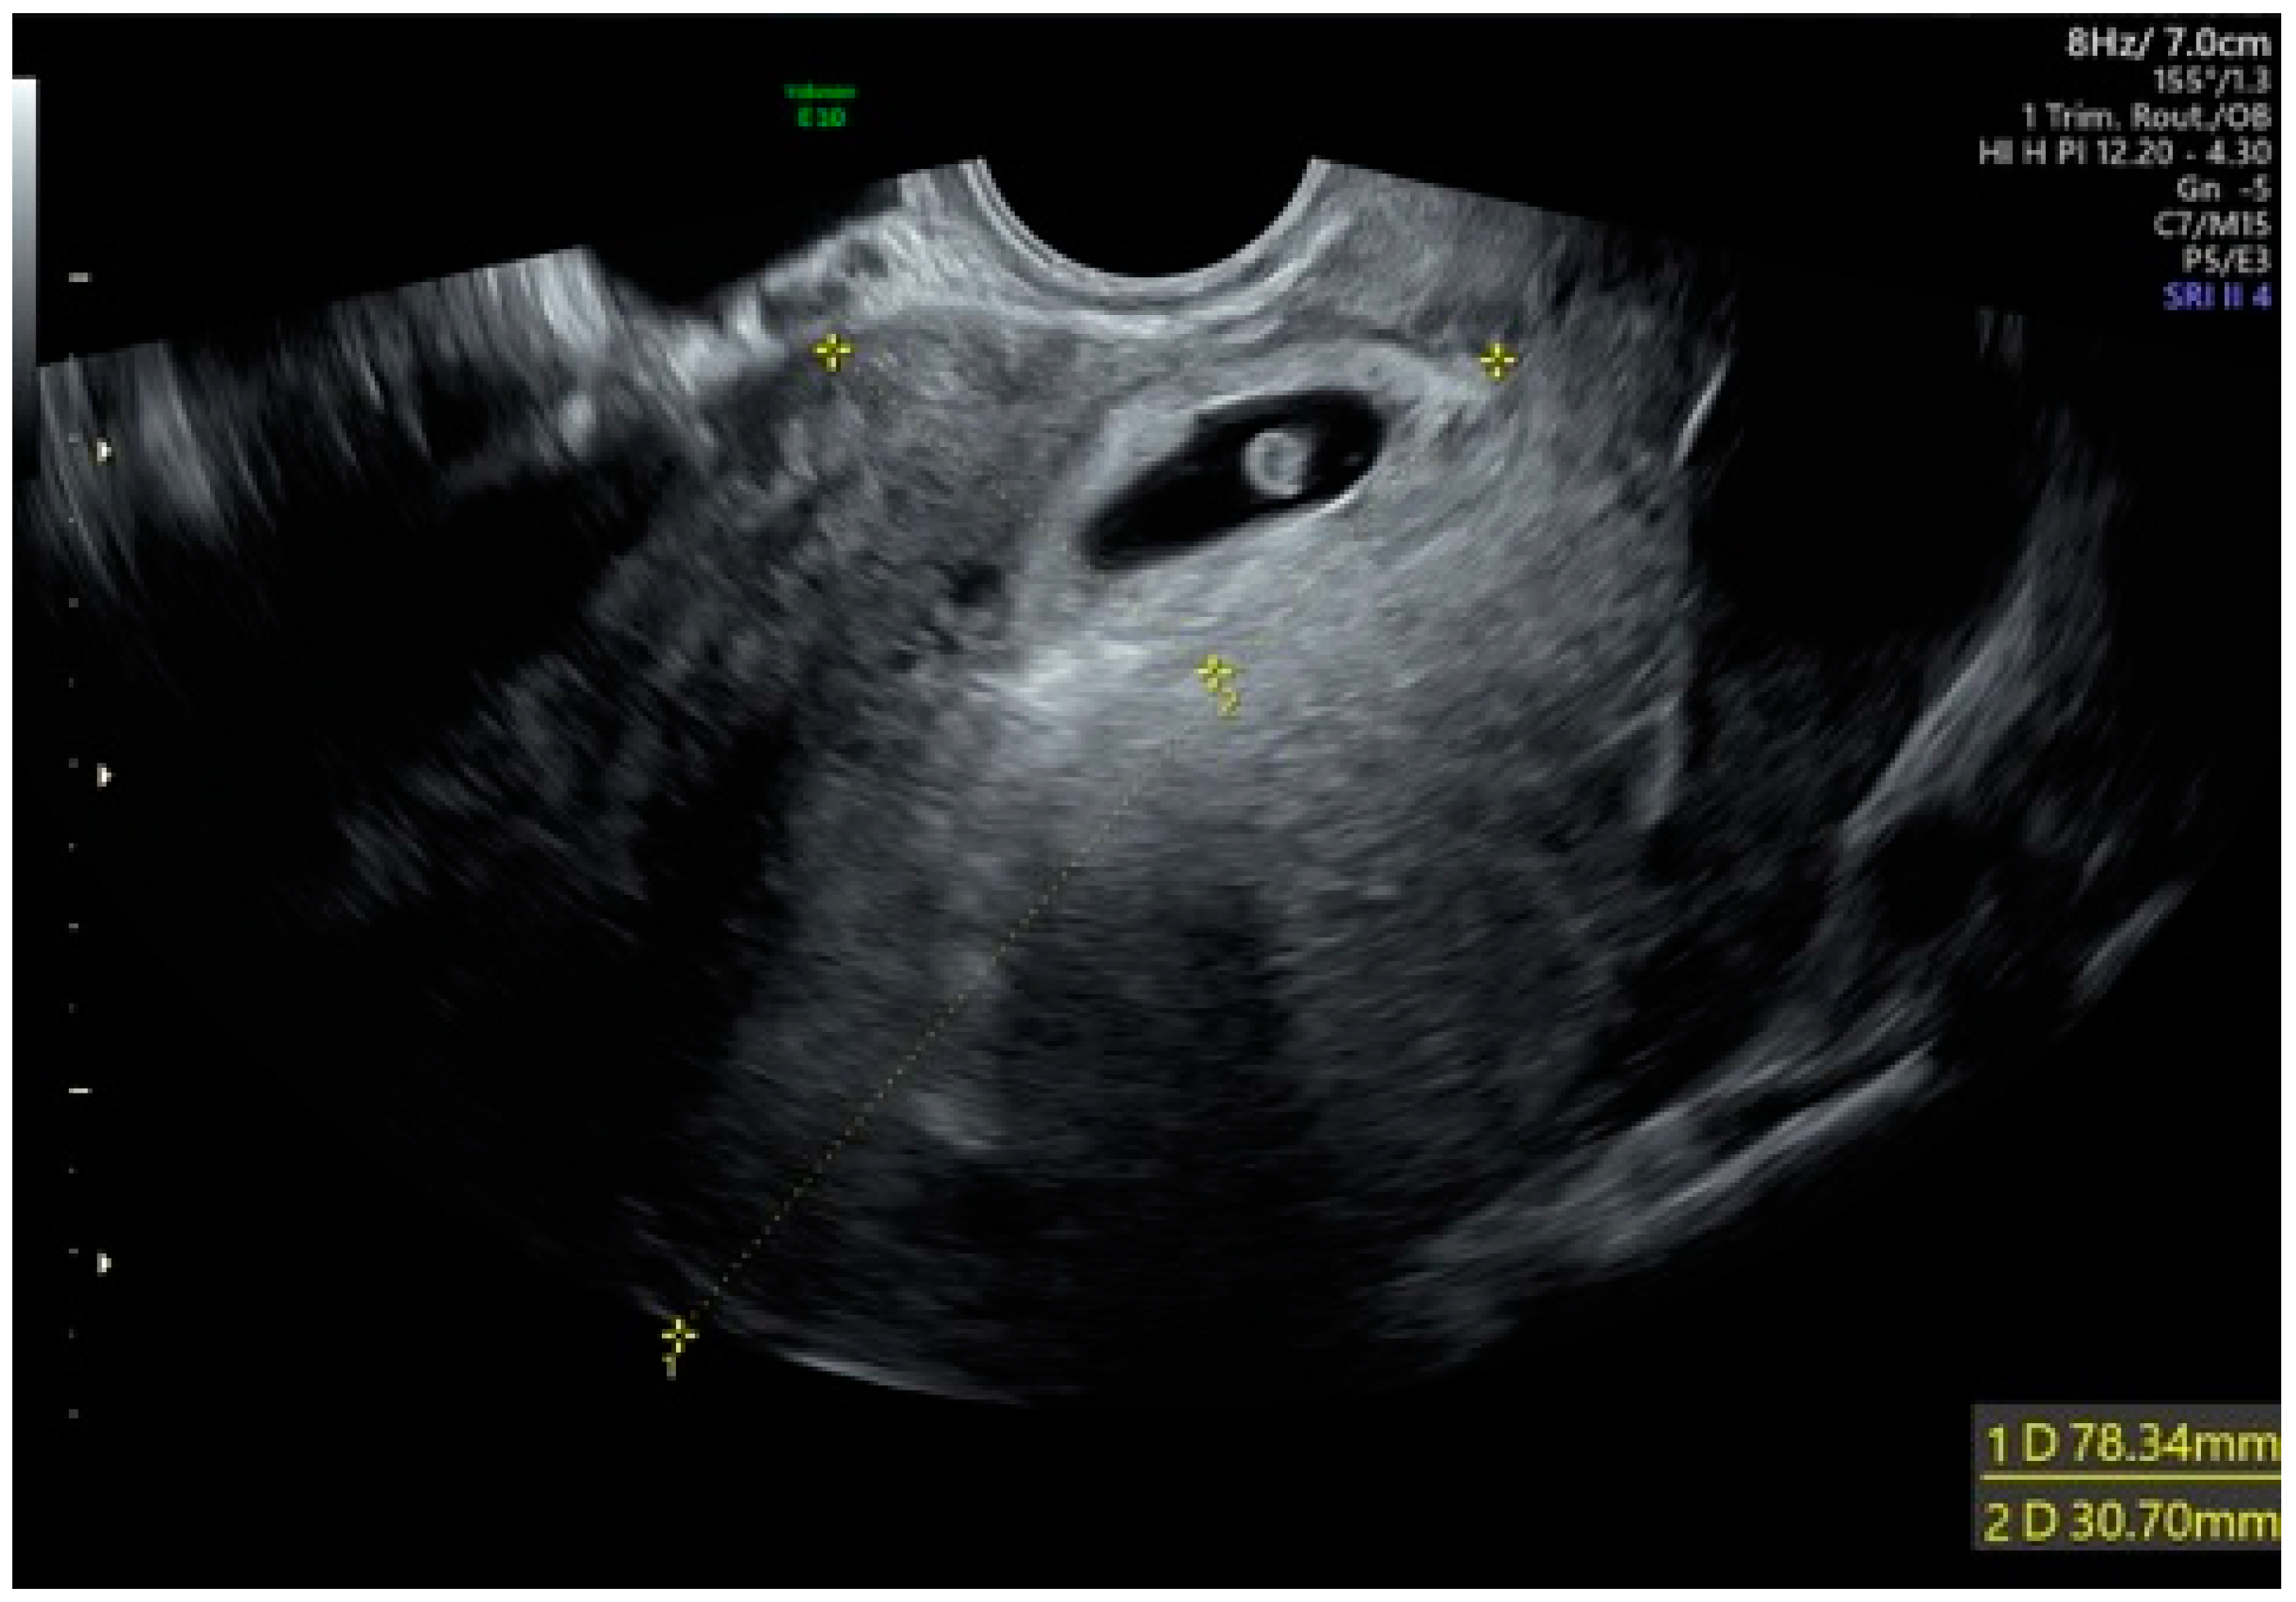

A 40-year-old woman with an amenorrhea of 5.5 weeks was admitted to the Department of Obstetrics and Gynecology of Foggia Hospital with acute onset of poor vaginal bleeding and mild cramping lower abdominal pain. Regarding her obstetric history, she had a normal vaginal delivery and two cesarean sections. The physical examination was remarkable only for the mild lower abdominal tenderness to deep palpation, a small amount of bleeding from the external cervical os, and a mild pain of the uterus. Laboratory data revealed a quantitative serum human chorionic gonadotropin level of 53,539 mIU/mL. A transvaginal ultrasound showed a gestational sac containing a yolk sac and an embryonic pole with cardiac activity (Figure 1), located in the anterior lower uterine wall near a previous cesarean scar. We repeated an ultrasound scan the day after the initial examination and confirmed a persistent gestational sac within the anterior uterine isthmus, close to the anatomic location of the previous cesarean scar (type 1, with preferential development of the pregnancy toward the uterine cavity). There was neither uterine bleeding nor any amount of blood in the abdominal cavity.

Figure 1. Cesarean scar pregnancy with cardiac activity.